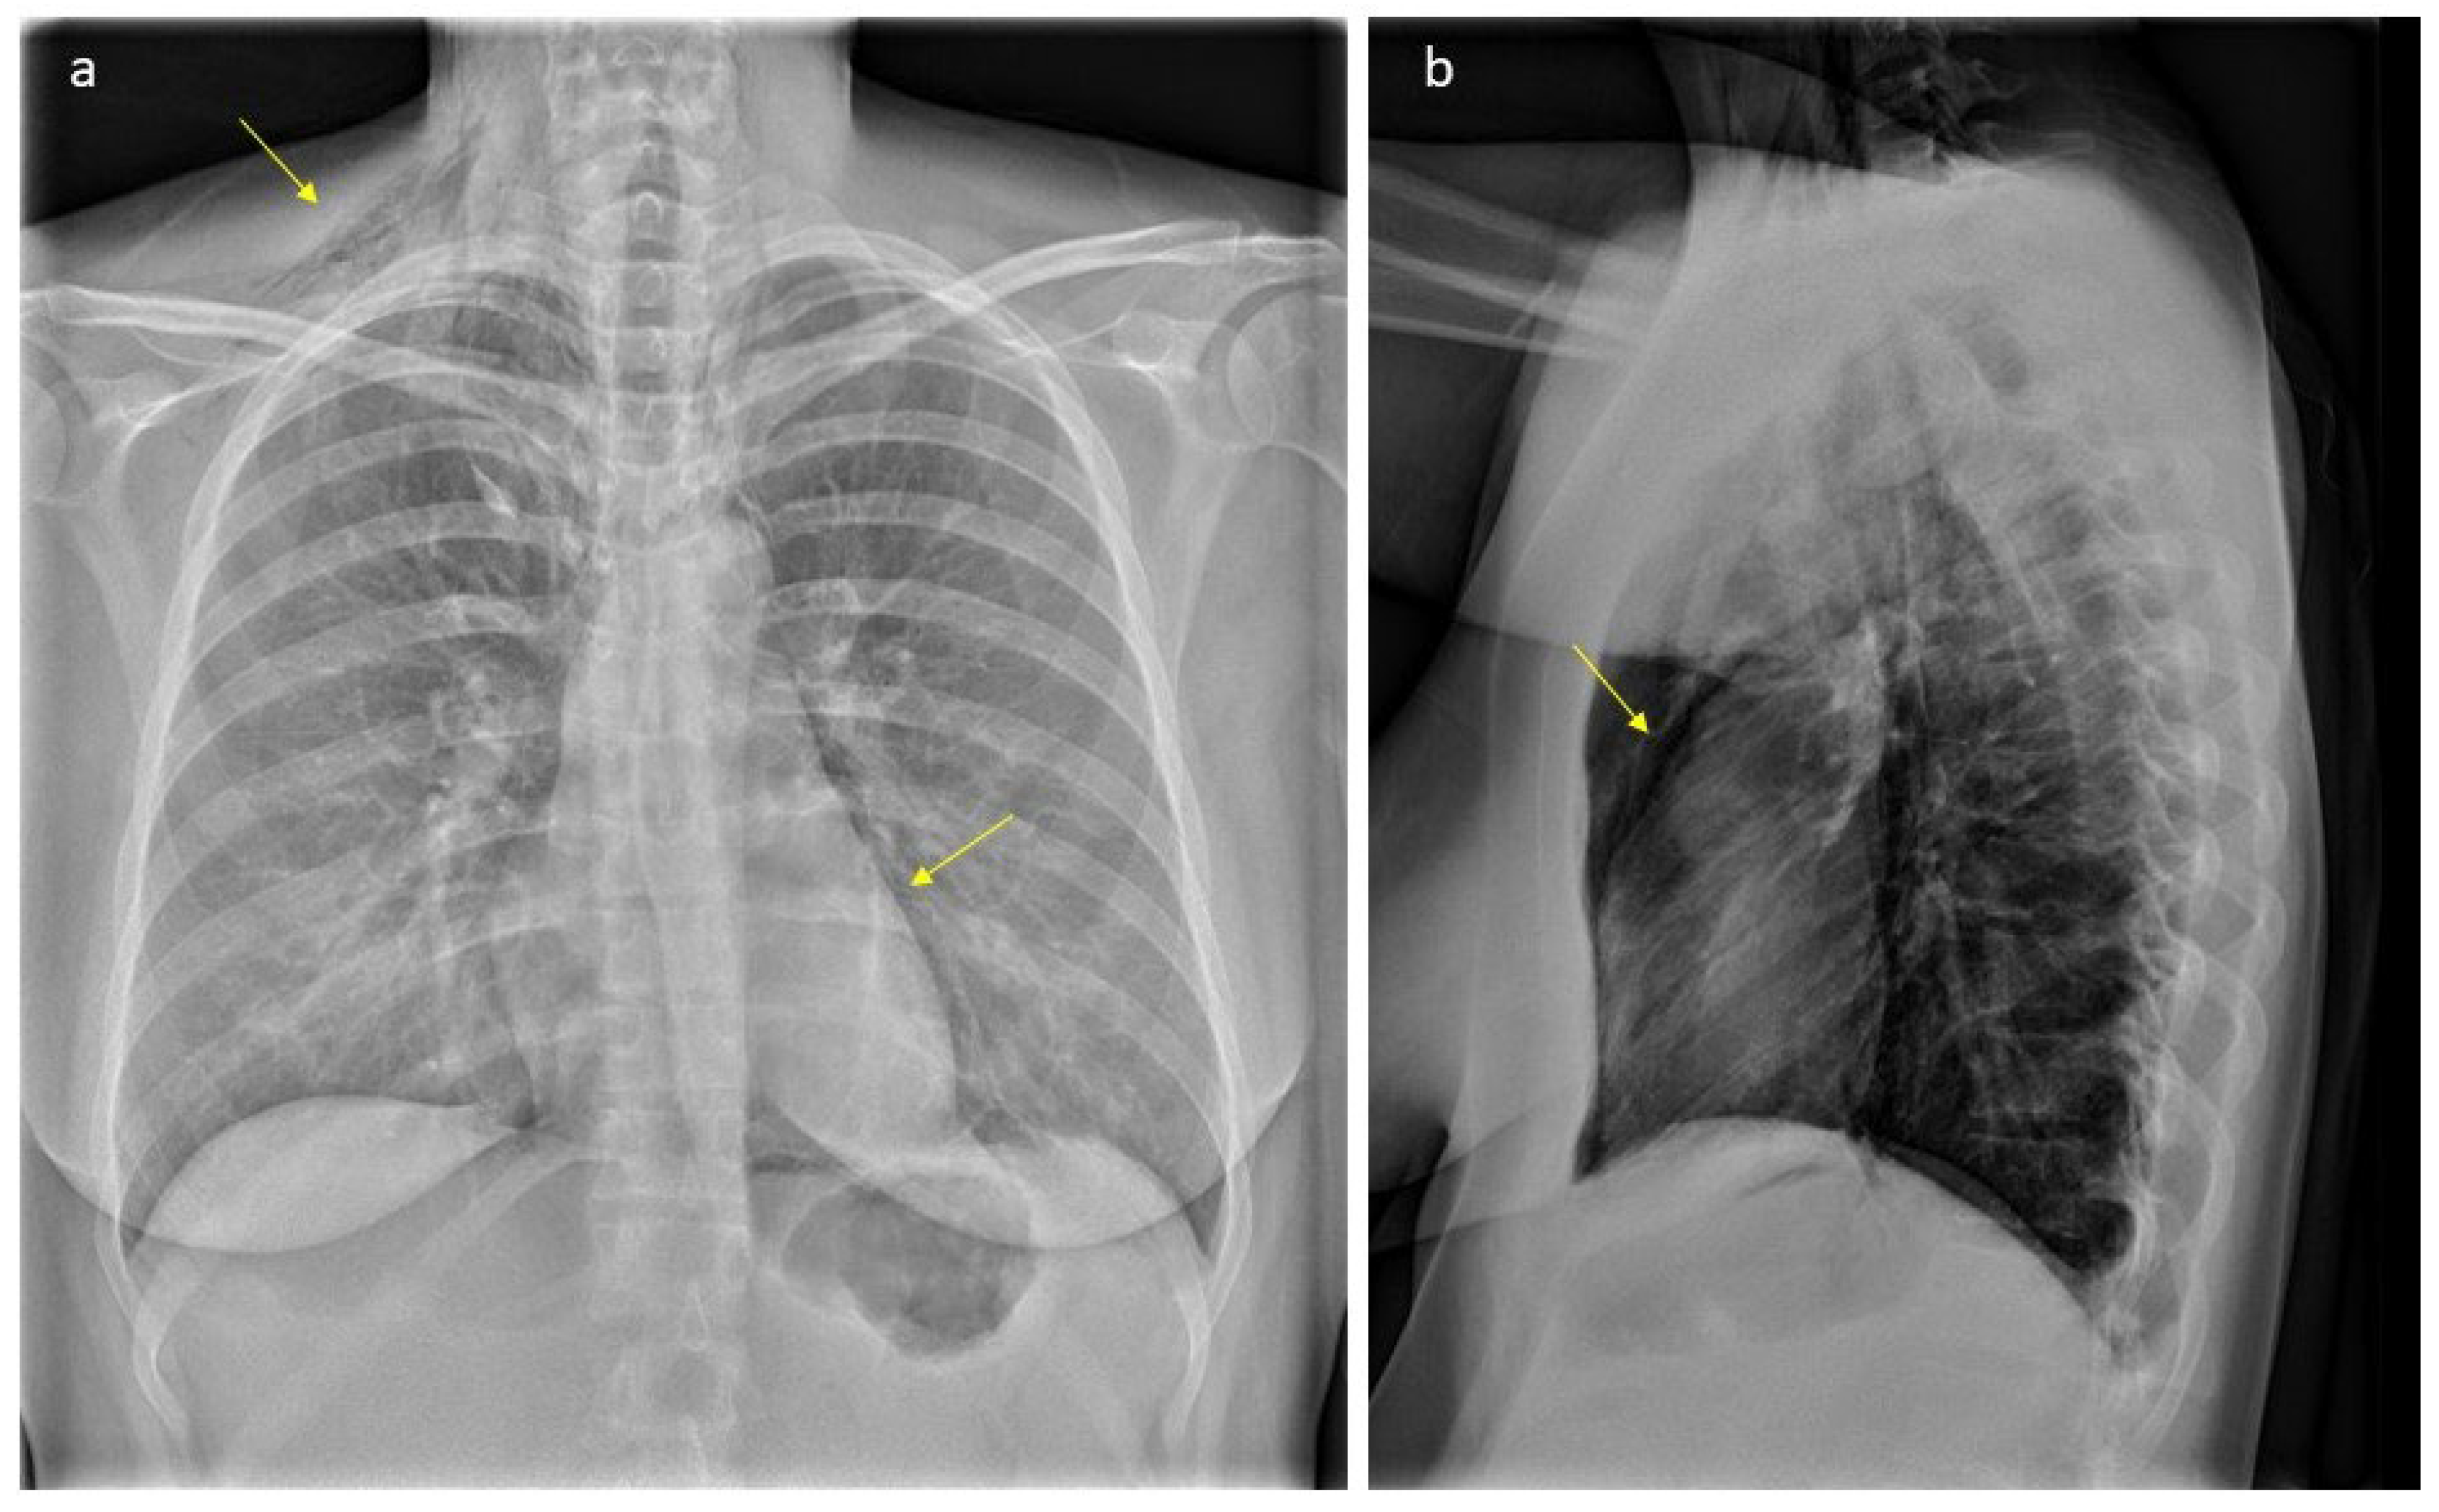

In the latent phase of delivery, she received morphine for analgesia. The water broke spontaneously, and the amniotic fluid was discolored. The patient had a normal temperature and there was no fetal tachycardia or other signs of fetal distress on cardiotocography (CTG). The active phase of labor lasted for three hours with normal progress. After one hour of passive descent, she started pushing, and the second stage lasted for 30 min. It was a spontaneous vaginal delivery of a healthy baby with a normal Apgar score (9-10-10) weighing 4170 g. There was a normal expulsion of the placenta, and there was normal bleeding. Eight hours after delivery, she complained of pain in the right ear, swelling and pain in the neck, chest tightness, shortness of breath, dysphagia, odynophagia, and pain in the upper thorax on the right side. Her vital signs were stable (BP 128/67 mmHg, pulse 91/min, temperature 36.0 °C, respiratory rate 14/min, and oxygen saturation 99% on room air). The ECG was unremarkable. Blood gas showed normal values with pH 7.45 and pCO2 4.2 kPa. A PCR test from the nasopharynx was negative for viral infections (analyzed for Adenovirus DNA, Chlamydia pneumoniae DNA, Coronavirus 229E RNA, Coronavirus NL63 RNA, Coronavirus OC43 RNA, SARS-CoV-2 RNA, Enterovirus RNA, Influenza A virus RNA, Influenza B virus RNA, Humant metapneumovirus RNA, Mycoplasma pneumoniae DNA, Humant parainfluenza virus 1 RNA, Humant parainfluenza virus 2 RNA, Humant parainfluenza virus 3 RNA, Humant parainfluenza virus 4 RNA, Bordetella pertussis DNA, Bordetella parapertussis DNA, Rhinovirus RNA, and Respiratorisk syncytial virus RNA). There were no findings on otoscopy. On palpation, there were subcutaneous crepitations in the neck, parasternal region, right axillary fossa, clavicle, and over the chest. Auscultation of the heart and lungs was normal. A chest X-ray (Figure 1) was taken immediately, revealing subcutaneous emphysema extending bilaterally to the neck but more prominent on the right side, and suspicious for pneumomediastinum. There were no signs of pneumothorax, esophageal, or skeletal pathology. The heart configuration was normal. The patient received 1 g of paracetamol and 2.5 mg of morphine intravenously. The situation was clinically stable. The next day, a CT scan (Figure 2) without contrast was performed, confirming pneumomediastinum, with air extending from the diaphragm up to the thoracic apexes and across the larynx. There were discreet amounts of pleural fluid bilaterally, and subcutaneous emphysema from the base of the skull to the neck and upper thorax.

Figure 1. Plain radiograph scan showing typical gas accumulations seen subcutaneously and with pneumomediastinum (arrows, part (a)): There is significant subcutaneous emphysema, more pronounced on the right side (arrow, part (a)). We can see an outlining of the pericardium both in lateral projection (arrow, part (b)) and with a “continuous diaphragm sign” on frontal projection (arrow, part (a)). You can also see continuous lucencies along upper mediastinum to the neck, through upper thoracic aperture.